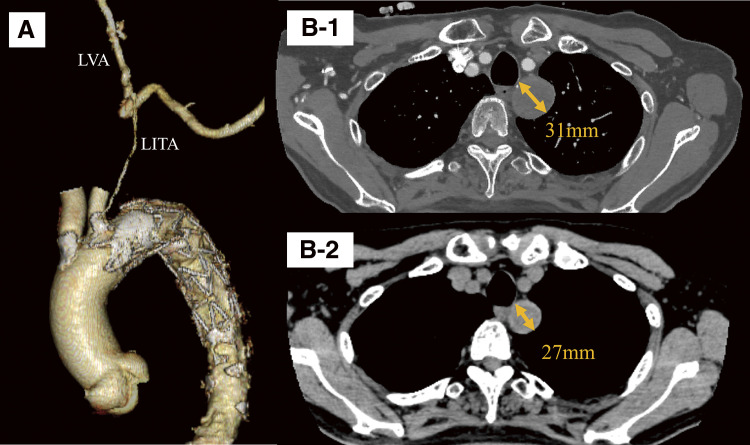

锁骨下动脉瘤是罕见且具有挑战性的治疗,由于其解剖位置和接近关键分支,包括椎动脉。我们报告的情况下,78岁的男子左锁骨下动脉瘤。动脉瘤位于纵隔,直径为31毫米。动脉瘤近端用支架封闭,远端通过锁骨上切口直接结扎。术后影像学证实完全排除。这种混合入路避免了侵入性开放手术,并提供了良好的结果。

Subclavian artery aneurysms are rare and challenging to treat owing to their anatomical location and proximity to critical branches, including the vertebral artery. We report the case of a 78-year-old man with a left subclavian artery aneurysm. The aneurysm was located in the mediastinum and measured 31 mm in diameter. The proximal side of the aneurysm was sealed with a stent graft, while the distal side was accessed through a supraclavicular incision and directly ligated. Postoperative imaging confirmed complete exclusion. This hybrid approach avoided invasive open surgery and provided a favorable outcome.